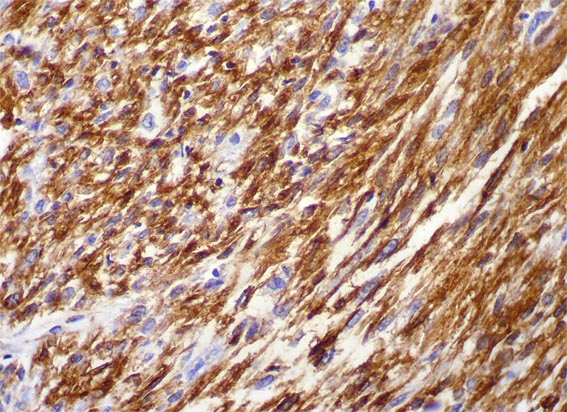

Figura 7.

IHQ para actina de músculo liso, X400.